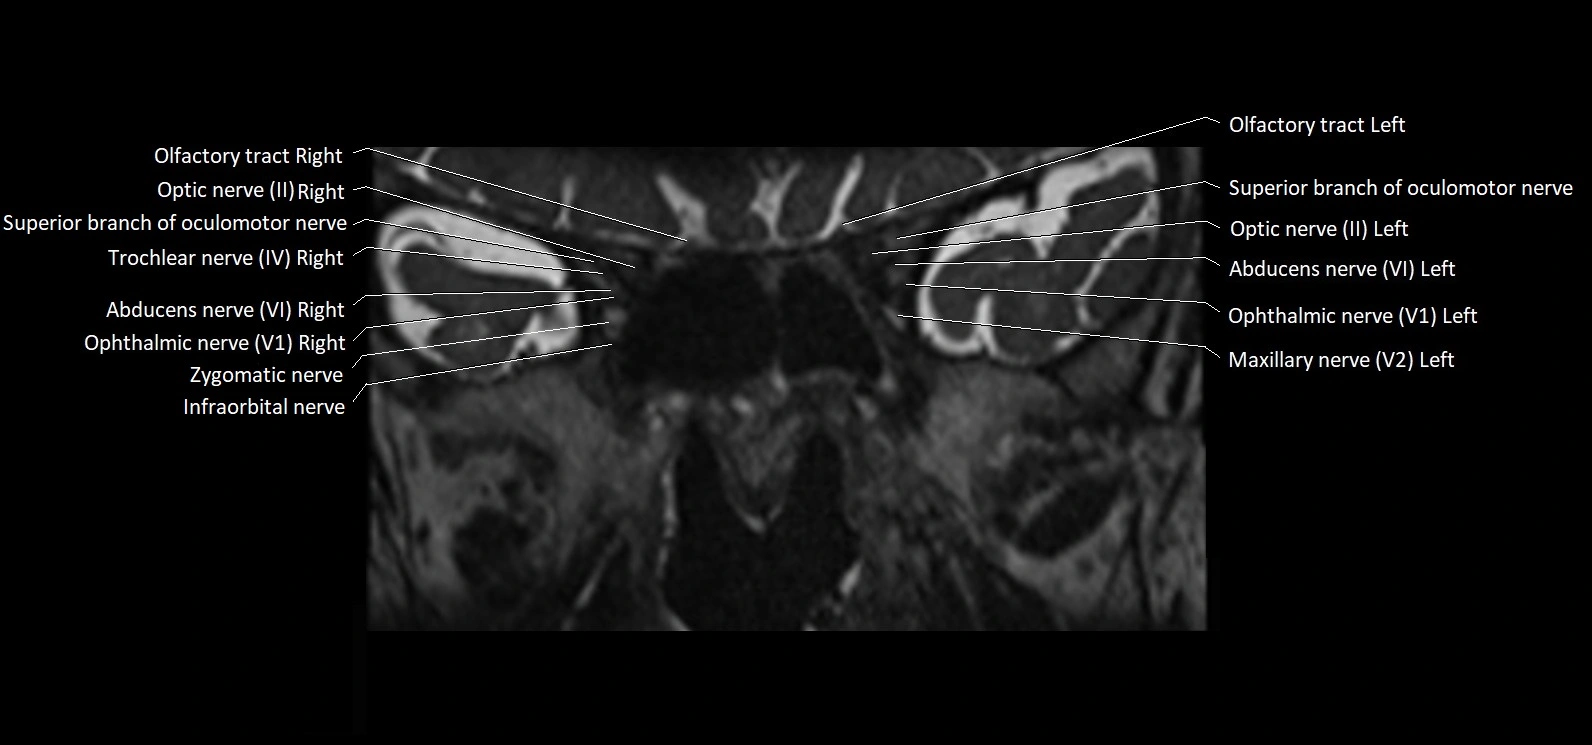

MRI images

image